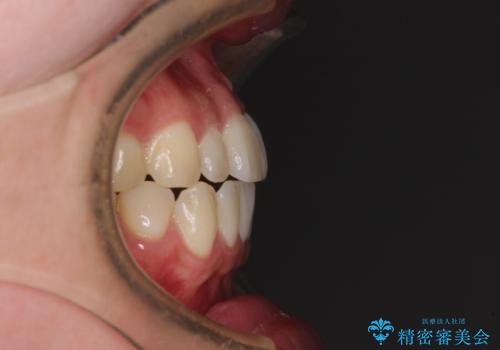

すきっ歯とオープンバイトをインビザラインで改善

- 前歯の上下スペースと前歯の隙間を気にして来院された患者様です。

インビザラインにより上下の前歯の隙間を閉じていくこととしました。

上下の隙間に舌が入り込むことが、すきっ歯やオープンバイトの原因であったため、舌の筋肉のトレーニングも並行して行い、後戻りの抑制を図りました。